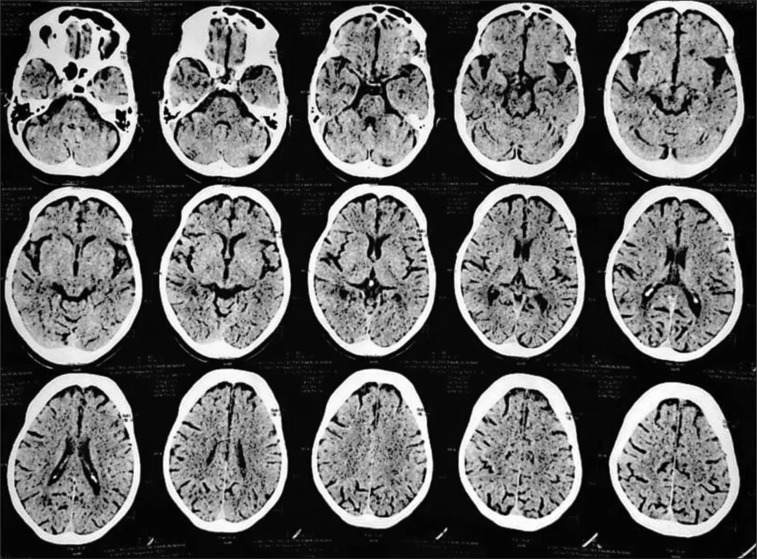

紧张症是一种以行动不便和交流障碍为特征的复杂综合征,在不同认知障碍和潜在痴呆的个体中,对劳拉西泮治疗的反应不同。本研究检查了一个病例系列,涉及四个不同的紧张性精神病患者,以阐明影响劳拉西泮反应的因素。虽然劳拉西泮作为一种gaba能调节剂,在某些情况下可以有效缓解症状,但其在其他情况下的有限影响突出了各种痴呆的潜在病理生理和治疗机制之间复杂的相互作用。本摘要提供了对神经化学通路、紧张症症状和治疗方法之间复杂关系的见解,揭示了在认知障碍和痴呆的背景下管理紧张症的复杂性。

Catatonia, a complex syndrome characterized by immobility and communication impairment, presents with varying responses to lorazepam treatment among individuals with different cognitive impairments and underlying dementias. This study examines a case series involving four distinct catatonic patients to elucidate the factors contributing to the variable lorazepam response. Although lorazepam, a GABAergic modulator, can effectively alleviate symptoms in some cases, its limited impact in others highlights the intricate interplay between the underlying pathophysiology of diverse dementias and treatment mechanisms. This abstract provides insights into the intricate relationship between neurochemical pathways, catatonic symptoms, and treatment approaches, shedding light on the complexities of managing catatonia in the context of cognitive impairments and dementias.